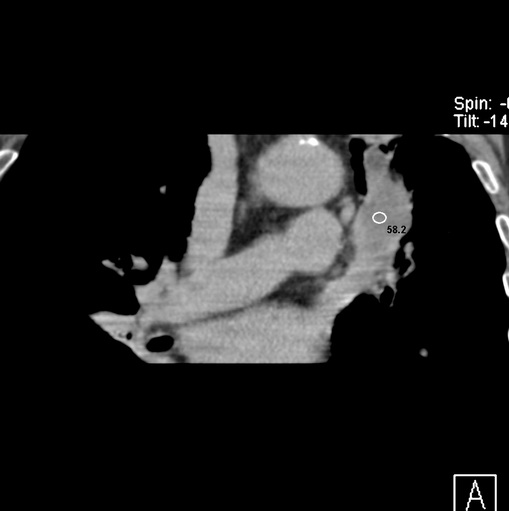

男性患者 81岁 咳嗽 咳痰 咯血

肿块贴近左肺门,包绕左上肺动脉,形态不规则。肿块增强扫描中度强化。纵膈内主动脉弓左旁间隙、气管隆突前、下间隙见多枚淋巴结影。综上考虑左侧中央型肺癌可能性大。图片没有完整上传,尤其是左肺上叶支气管分支层面没有上传,因此不好判断是叶支气管中断还是段支气管中断。另外,下图红色部分所示是“黏液支气管征”吗?